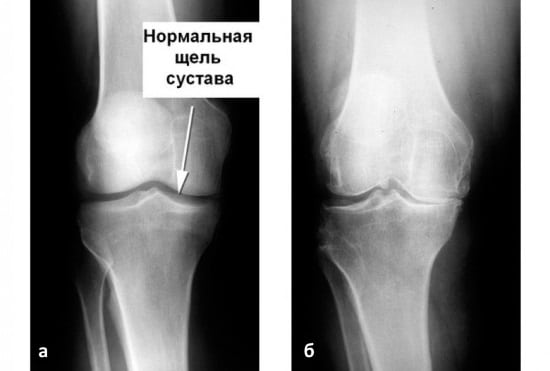

Основаниями для выставления диагноза становятся жалобы пациентов, результаты внешнего осмотра и рентгенографии. Это инструментальное исследование наиболее информативно, но при остеоартрозе 1 степени характерные признаки могут отсутствовать. На конечном этапе заболевания 1 рентгенологической стадии обнаруживаются единичные остеофиты, сужение суставной щели и уплотнение субхондральной зоны.

При неинформативности рентгенографических снимков могут быть назначены МРТ, КТ, УЗИ. На полученных изображениях хорошо визуализируются хрящевые ткани, связочно-сухожильный аппарат, кровеносные сосуды, нервные стволы.

Остеоартроз медленно, но упорно прогрессирует. Его течение осложняется вторичными реактивными синовитами, спонтанными кровоизлияниями в полость сустава (гемартрозами), остеонекрозом мыщелка бедра, наружными подвывихами надколенника. На 4 рентгенографической стадии суставная щель сращивается, что приводит к полному или частичному обездвиживанию.